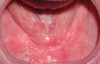

Palatal and vestibular depth influences the available ridge height present (Figure 2). When a standard denture or overdenture is on the arch, the act of chewing encompasses both a vertical and horizontal motion that place lateral forces on the prosthesis. The denture/overdenture flanges are in contact with the remaining ridge. The higher the ridge, the more lateral bracing occurs during chewing and the less displacement of the prosthesis from the arch laterally (Figure 3). Yet, when a low ridge height is available—either due to a shallow palate or vestibule or combination of these—the ridge has minimal effect at bracing against lateral displacement (Figure 4). This increases lateral loading and the shear loads placed on freestanding implants. When these anatomic factors are noted during the initial examination, the patient should be made aware of the need for splinting the implants with a bar to assist in distributing the loading forces over the entire arch and to shield the individual implants from shear loading. Patients who have shallow vestibules but adequate vestibular depth have two options regarding the prosthetics (Figure 5). If freestanding implants are to be used, maintaining palatal coverage may be needed. This may not require full palatal coverage, and depending on the anatomy, eliminating the posterior one-third may be possible while maintaining the anterior two-thirds to aid in stability via a hard stop on the non-movable anterior palate when the patient occludes. As stated earlier, lateral loads are not handled as well as loads directed along the implant’s long axis, and during chewing, lateral loading occurs on implants and natural teeth. In the edentulous arch, typically, there is not 1 implant per missing tooth and the arch may only have 4 to 6 implants present. This lateral loading during chewing will not have the lateral surfaces of the ridge to brace from these forces, and all loads are placed on the implants when the arch has shallow vestibules, palate, and floor of the mouth. One of the biggest challenges in fully edentulous cases is the available interarch vertical height, which does have an effect on prosthetic design.2

Fig 4. Maxillary arch demonstrating shallow vestibular vault and vestibular depth.

Figure 4